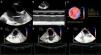

Lactante de 42 días de vida trasladado con diagnóstico de miocardiopatía dilatada idiopática (fig. 1). La fracción de eyección (FE) del ventrículo izquierdo (VI), como marcador pronóstico, fue evaluada por Modo M, Simpson biplano y strain 2D.

Miocardiopatía dilatada severa. A) Plano paraesternal largo que muestra dilatación severa del ventrículo izquierdo. B) Cuantificación del diámetro, espesor de paredes y función ventricular izquierda por Modo M. C) Strain 2 D longitudinal. Representación en «ojo de buey» de la deformación miocárdica del ventrículo izquierdo. D, E, F) Strain 2D longitudinal en tres proyecciones apicales: plano 4 cámaras, 2 cámaras y 3 cámaras, respectivamente.

Se calculó el valor de strain global longitudinal y FE del VI por técnica speckle tracking en proyección apical (fig. 1) y se fue comparando evolutivamente con los resultados obtenidos mediante otras técnicas (fig. 2).